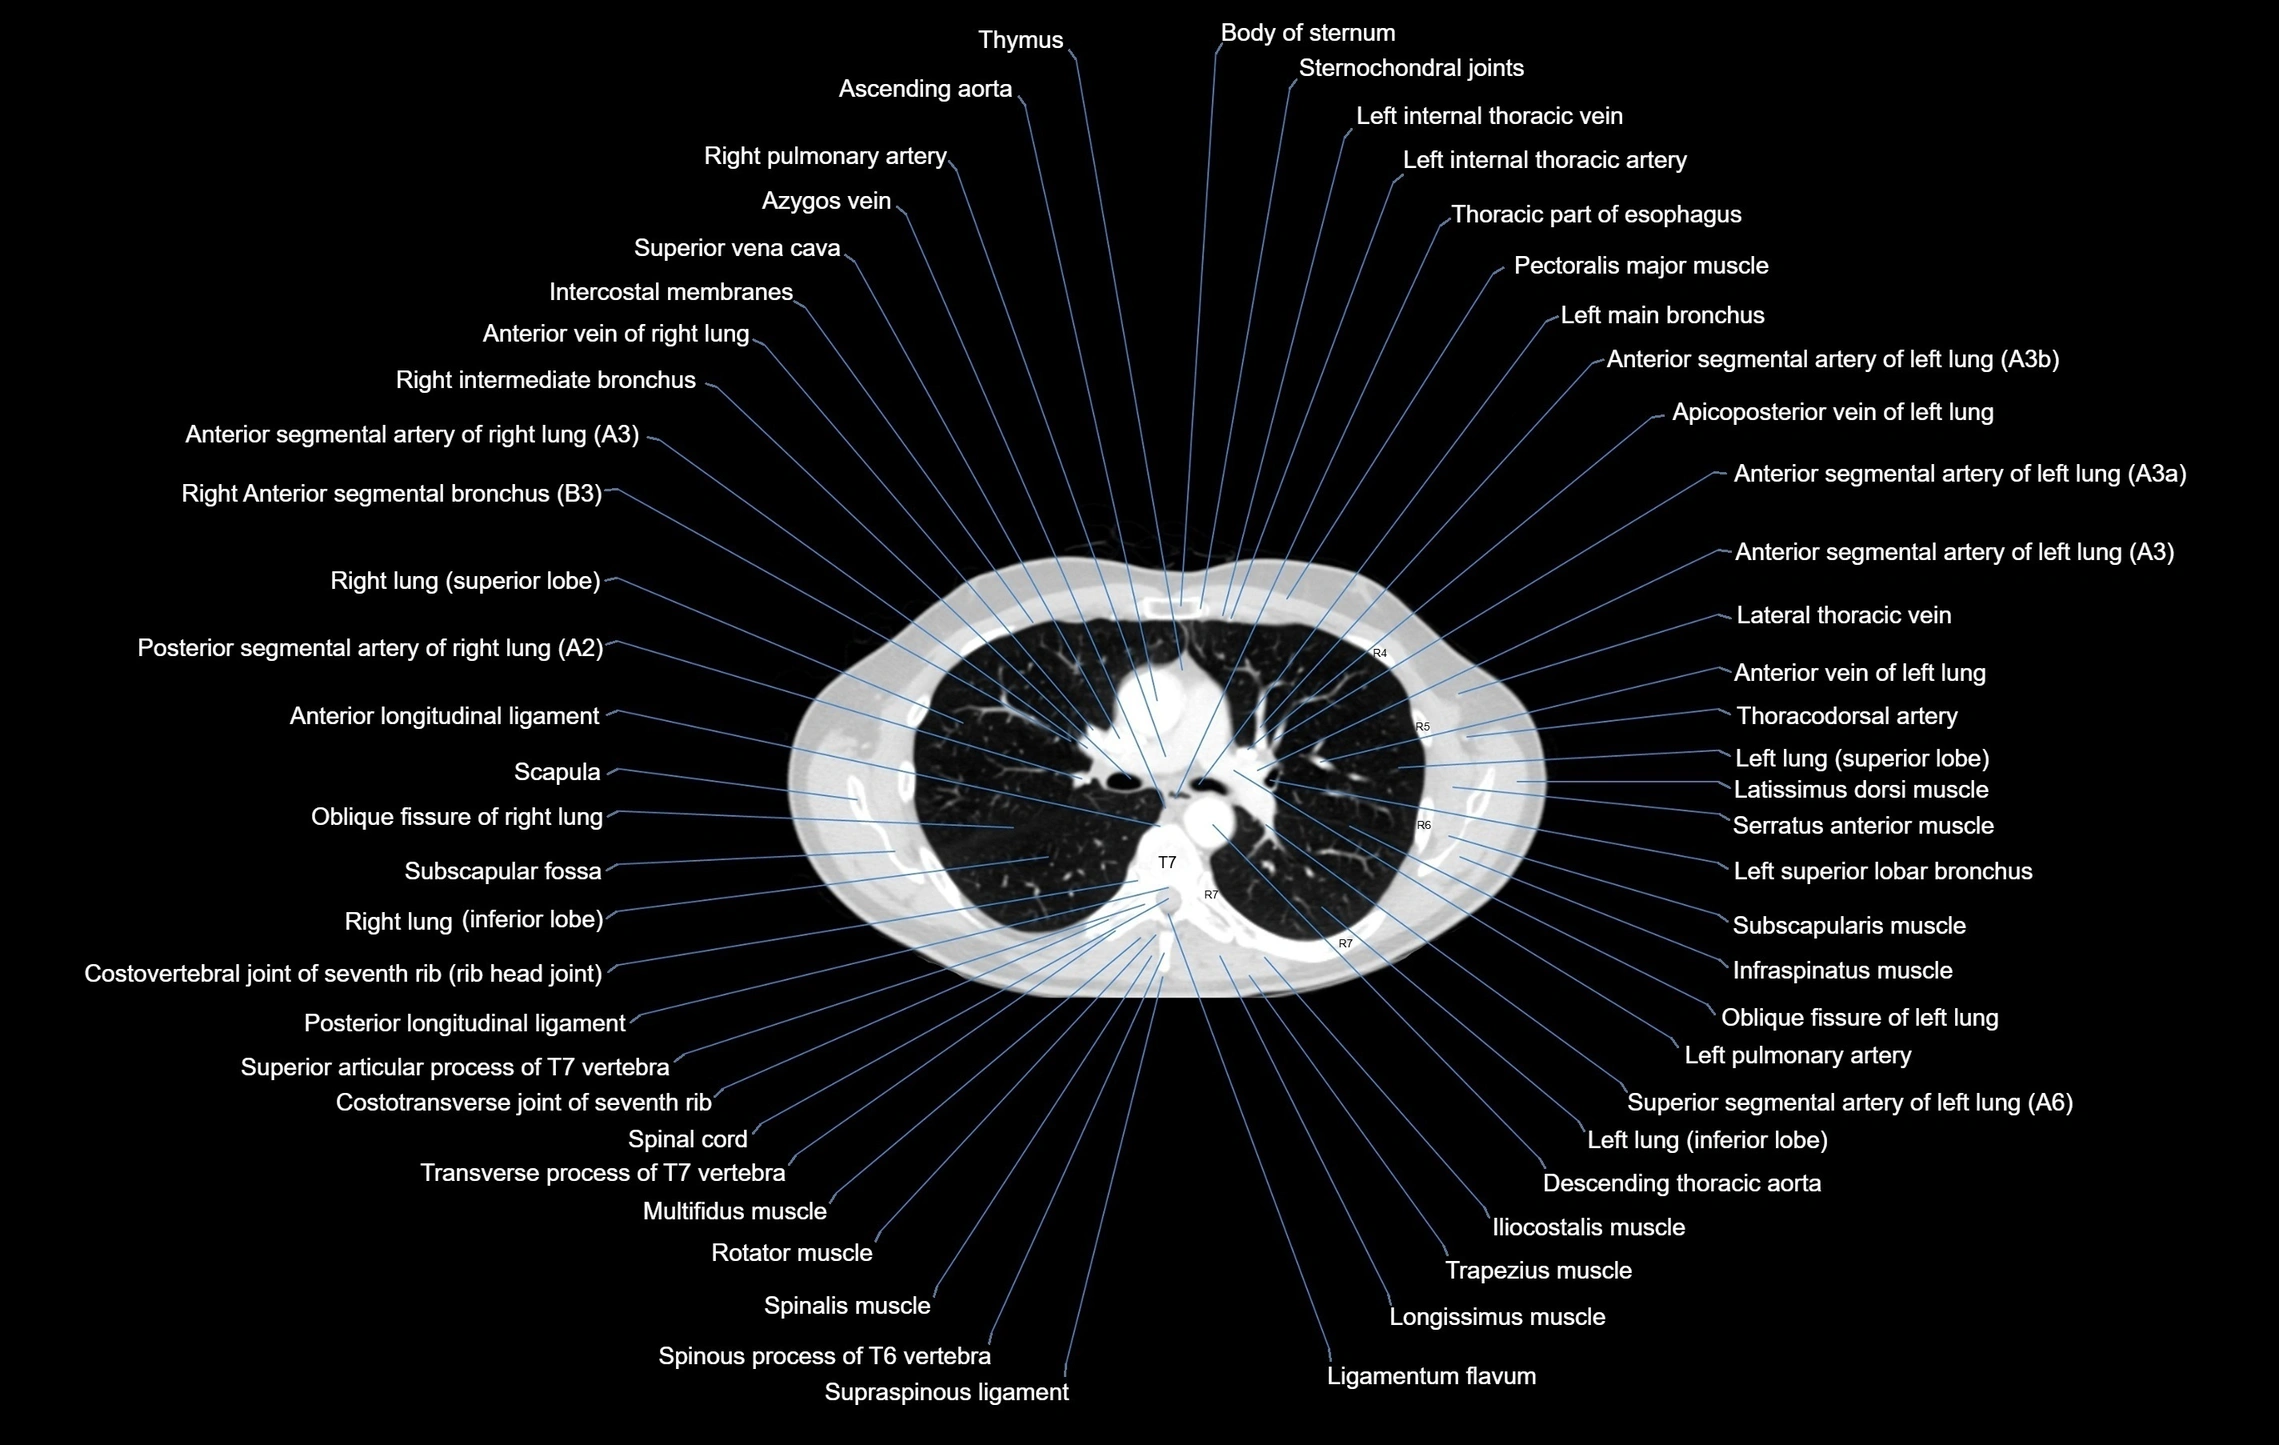

- Ascending aorta

- Right pulmonary artery

- Azygos vein

- Superior vena cava

- Left main bronchus

- Left pulmonary artery

- Descending thoracic aorta

- Scapula

- Infraspinatus muscle

- Subscapularis muscle

- Trapezius muscle

- Latissimus dorsi muscle

- Serratus anterior muscle

- Multifidus muscles

- Posterior longitudinal ligament

- Ligamenta flava (Ligamentum flavum)

- Anterior longitudinal ligament